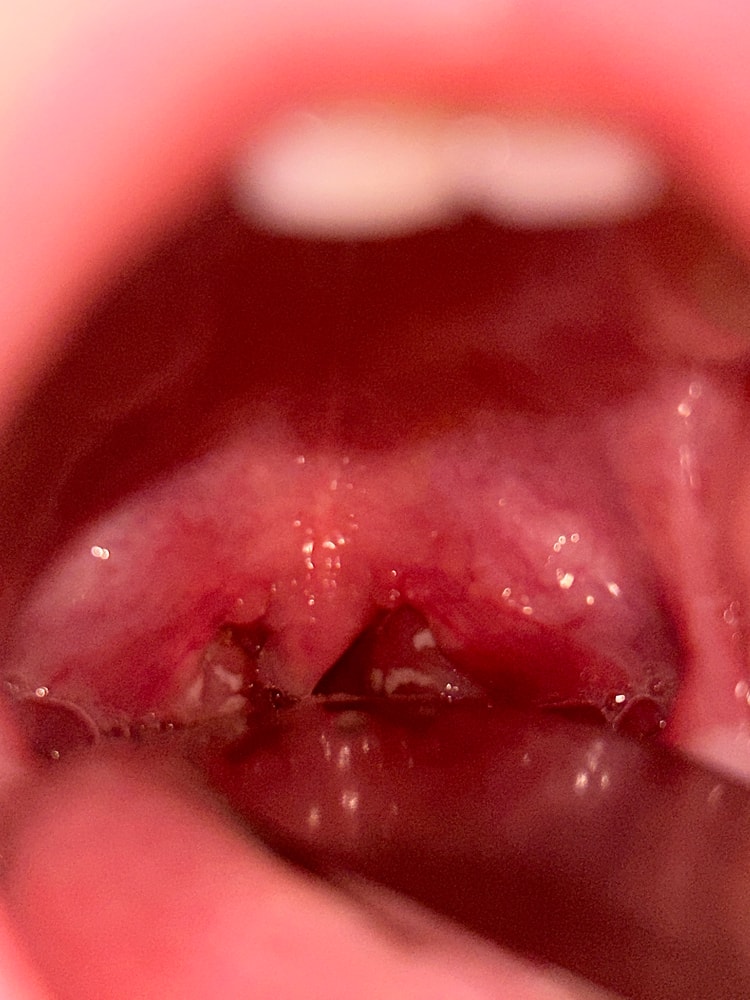

Фото с горлом на второй день заболевания

Libe, оно его изначально не беспокоило,но у него изменился голос и он кашлял,но кашель был именно горловой,но не как при ларинготрахеите,насморк,а еще жаловался что очень устал,прям весь день чуть поиграет и устал,начали горло смотреть,а там будто лакунарная ангина,поехали срочно к Лору,лор назначил панцеф.На чувствительность сдавали,именно цефиксима нет в списке,но врач сказал что все равно правильно подобрали.Налет еще есть в небольшом количестве,в глубине.